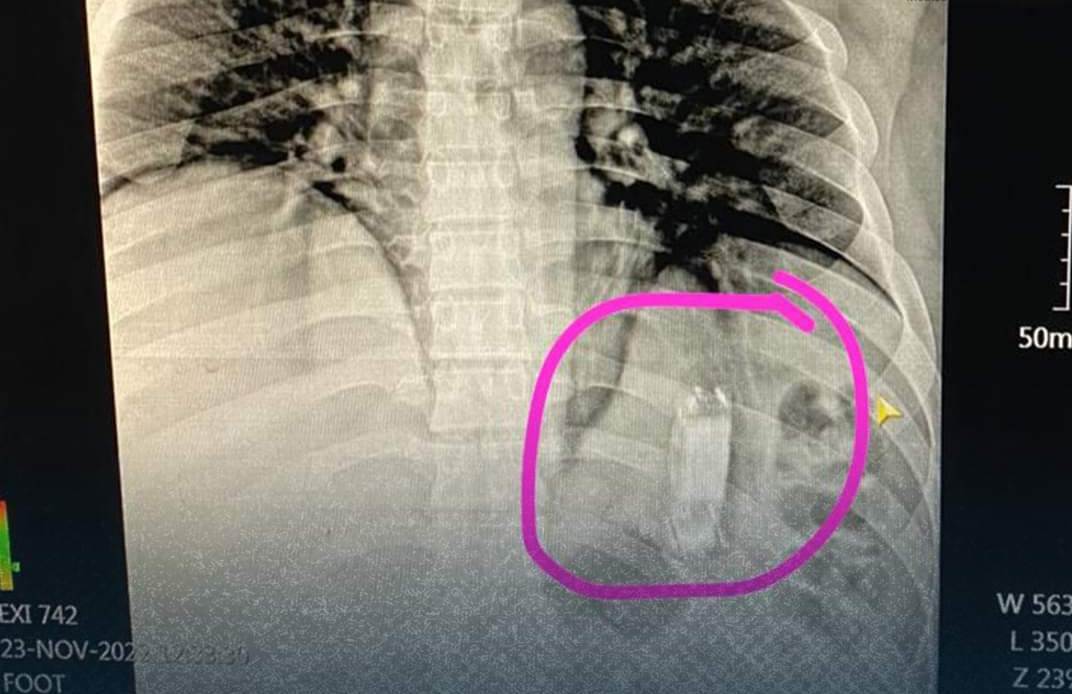

حيث استقبل المستشفى شاب يبلغ 40 عامًا، يعاني من آلام في المعدة وقيء، وبإجراء الكشف الطبي عليه وعمل الأشعات والفحوصات الطبية اللازمة، تبين وجود جسم غريب داخل المعدة.

وتمكن أطباء وحدة مناظير الكبد الجهاز الهضمي بالمستشفى، من استخراج الجسم باستخدام منظار المعدة والمرئ، وتبين أنه هاتف محمول ابتلعه المريض.